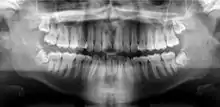

Panoramic radiograph

A panoramic radiograph is a panoramic scanning dental X-ray of the upper and lower jaw. It shows a two-dimensional view of a half-circle from ear to ear. Panoramic radiography is a form of focal plane tomography; thus, images of multiple planes are taken to make up the composite panoramic image, where the maxilla and mandible are in the focal trough and the structures that are superficial and deep to the trough are blurred.

![]() A dental panoramic radiograph, showing the maxilla and mandible, all the teeth including the "wisdom teeth," the frontal and maxillary sinuses, the nasal cavity and the temporomandibular joint and other near by head and neck anatomy. | |